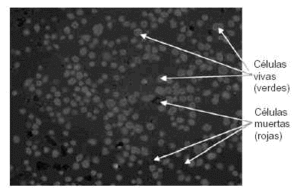

En las instalaciones del Instituto de Ortopedia, que cumplen estrictamente toda la normativa GMP que hemos expuesto, se ha establecido el obligatorio manual de calidad del producto que incluye el control riguroso de todo el proceso de cultivo y hace especial hincapié en el control automatizado del número de células y viabilidad de las mismas para cada cultivo de condrocitos (Fig. 5).

Figura 5. Control automatizado por ordenador de las viabilidad celular.

De igual manera, se realiza un control de la capacidad de rediferenciación de las células mediante su inclusión en matrices de alginato y análisis de la expresión de los genes del colágeno II y X como ya vimos (Figs. 1 y 2). También se controla el grado de hipertrofia de los condrocitos, proceso que normalmente acompaña al de desdiferenciación, durante su cultivo. Este control se realiza empleando un contador celular que indica la distribución de tamaño de las células que van a ser implantadas en el paciente.